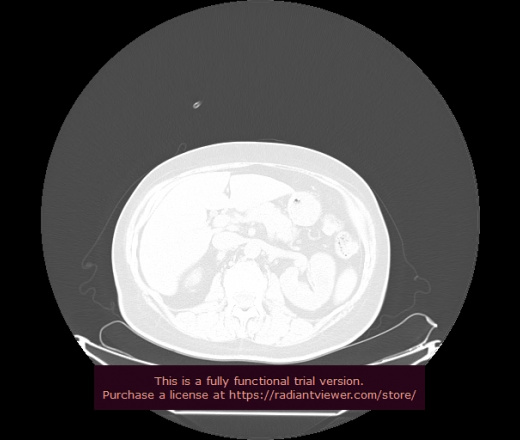

Уважаемые коллеги, если имеется интерес, сможете ли Вы спрогнозировать дальнейшее +-одинаковое течение процесса у 4 данных разных пациентов? Зацепиться где-то можно очень просто, где-то нельзя.